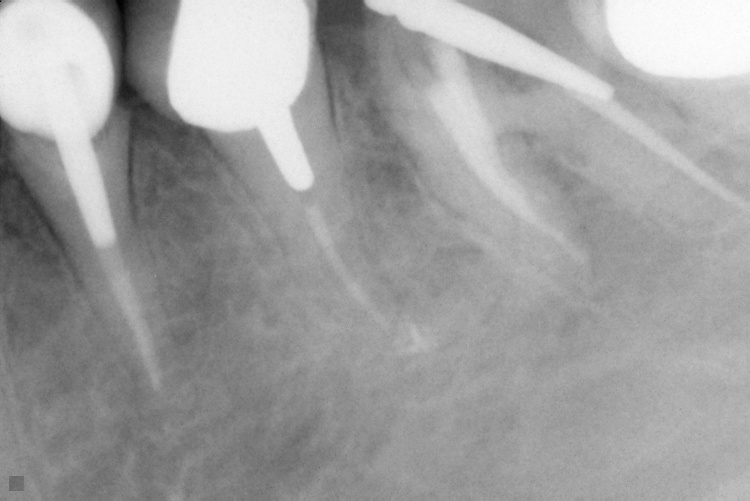

Name Last modified Size Description Parent Directory - IO000001.jpg 2020-07-28 14:20 84K IO000002.jpg 2020-07-28 14:20 82K IO000003.jpg 2020-07-28 14:20 85K IO000004.jpg 2020-07-28 14:20 82K IO000005.jpg 2020-07-28 14:20 84K